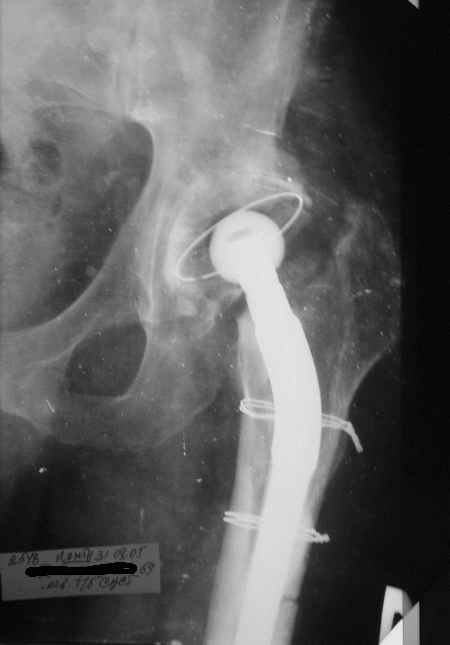

Уважаемые коллеги,Мужчина, 69 лет, в декабре 2004 г перенес тотальную цементную артропластику . Через 3 мес после операции на фоне прогрессирующих болей в средней и проксимальной третях бедра при нагрузке возникли резкие боли и появилось опухолевидное болезненно образование. Процесс сопровождался резким одномоментным укорочением ноги.

В феврале 2005 г. выполнена ревизионная артропластика, завершившаяся прогрессировавшим в течение 1-2 мес укорочением ноги. В настоящее время ходит только с костылями, при движениях в тазобедренном суставе испытывает резкие боли, ощущает хруст. Попытка осевой нагрузки бедра сопровождается ощущением "перемещения поршня" и заметным по внешним ориентирам укорочением левой ноги на 1-1,5 см.

Наверное перфорация стенки при первичном протезировании и неадекватный размер Вагнера при ревизионном? Что-нибудь еще?

Я полностью поддерживаю Ваше мнение об интраоперационной перфорации при первичном протезировании, т.к. при внимательном рассмотрении рентгенограммы после этого этапа виден дефект кортикального слоя именно по задне-наружной поверхности .

И ножка Вагнера подобра плохо, и насчет возможной инфекции Вы совершенно правы, т.к. рана после второй операции заживала вторичным натяжением.

К сожалению, Р-граммы не захватывают полностью бедро, поэтому окончательное решение может быть после полноценного р-ского обследования. Однако думаю, что оптимальное решение - полнопокрытая ножка длинной не менее 200 мм, без привязки к типу протеза. Это может быть модульная система ZMR, Solution и др., главное - принцип. В отношении чашки тоже есть определенные сомнения. Думаю, что наш ин-т (РосНИИТО, СПб) смог бы сделать эту операцию.

Ситуация достаточно несложная. Основной массив бедренной кости сохранён. Лучше поменять чашку сразу, потому что ей не долго осталось жить. Слишком латерально поставлена. Предпочитаю RM чашки при ревизии. Ножка предпочтительней Solution. Если есть проблемы по замене, могу взять к себе без проблем.